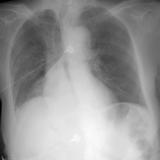

RLL Collapse 1 PA

Date: 02/28/2004

Views: 3360